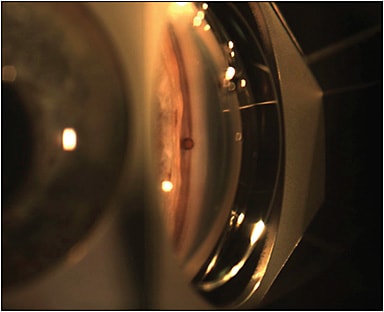

The SOLX Gold Shunt (SOLX Inc.) is a 24-karat-gold suprachoroidal implant for the treatment of primary open-angle glaucoma (POAG) with or without cataract surgery. The shunt is implanted through scleral incision and dissection; the proximal end of the long rectangular plate is positioned in the anterior chamber to provide ingress for aqueous humor, while the distal end remains in the suprachoroidal space to promote drainage of the fluid from the anterior chamber to the suprachoroidal space.2 The SOLX Gold Shunt received the European CE mark in 2005 and is cleared for use in Canada, although its inflammatory effects have prevented FDA approval and use of this device in the United States (Figure 1).